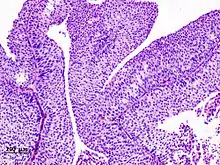

_pT1.JPG.webp)